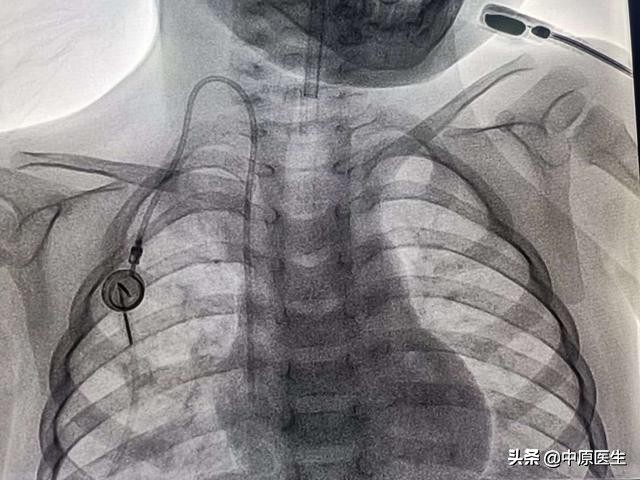

今天,再创了我们介入科植入静脉输液港最小年龄新纪录——2岁(以前记录是3岁)。这个新纪录创造的有些让人心塞,这是一个小小年纪就需要长期接受化疗的孩子,但是,外周的血管已经没一个好扎的了,常规深静脉置管技术如CVC、PICC全试过了,无法完成任务!最后决定尝试静脉输液港。

麻醉顺利,克服困难,穿刺成功,最后顺利植入静脉输液港,植入式静脉输液港是一种完全植入的血管通道系统,它为患者提供长期的静脉血管通道。